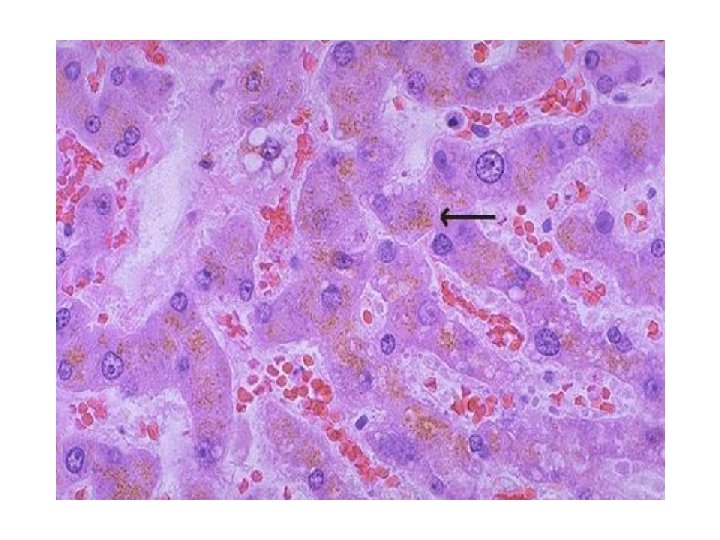

Nekroz tipleri: • Koagülasyon nekrozu (Beyin dışı dokularda, hipoksiye bağlı hücre ölümünün karakteristik görüntüsüdür. ) Doku çatısı bir süre de olsa korunur. • Likefaksiyon nekrozu (Beyinde hipoksiye bağlı hücre ölümünün karakteristik görüntüsüdür + Enfeksiyöz durumlarda) • Kazeifikasyon nekrozu (Ör: tüberküloz) • Yağ nekrozu (yağ dokusunu oluşturan hücrelerin ölümündeki görüntüdür. )

Likefaksiyon Nekrozu Kazeifikasyon Nekrozu Yağ Nekrozu